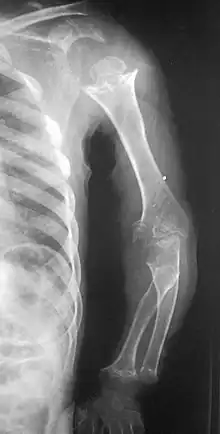

| Pseudoachondroplasia. Shoulders and Humeri. Note the dysplastic proximal humeral epiphyses, metaphyseal broadening, irregularity and metaphyseal line of ossification. These changes are collectively known as "rachitic-like changes". Lesions are bilateral and symmetrical. | |

Skeletal radiography

Accurate assessment of plain radiographic findings remains an important contributor to diagnosis of pseudoachondroplasia. It is noteworthy that vertebral radiographic abnormalities tend to resolve over time. Epiphyseal abnormalities tend to run a progressive course. Patients usually suffer early-onset arthritis of hips and knees. Many unique skeletal radiographic abnormalities of patients with pseudoachondroplasia have been reported in the literature.[2][7][4]

- Together with rhizomelic limb shortening, the presence of epiphyseal-metaphyseal changes of the long bones is a distinctive radiologic feature of pseudoachondroplasia.

- Dysplastic/hypoplastic epiphyses especially of shoulders and around the knees.

- Metaphyseal broadening, irregularity and metaphyseal line of ossification. These abnormalities that are typically encountered in proximal humerus and around the knees are collectively known as “rachitic-like changes”.

- Radiographic lesions of the appendicular skeleton are typically bilateral and symmetric.